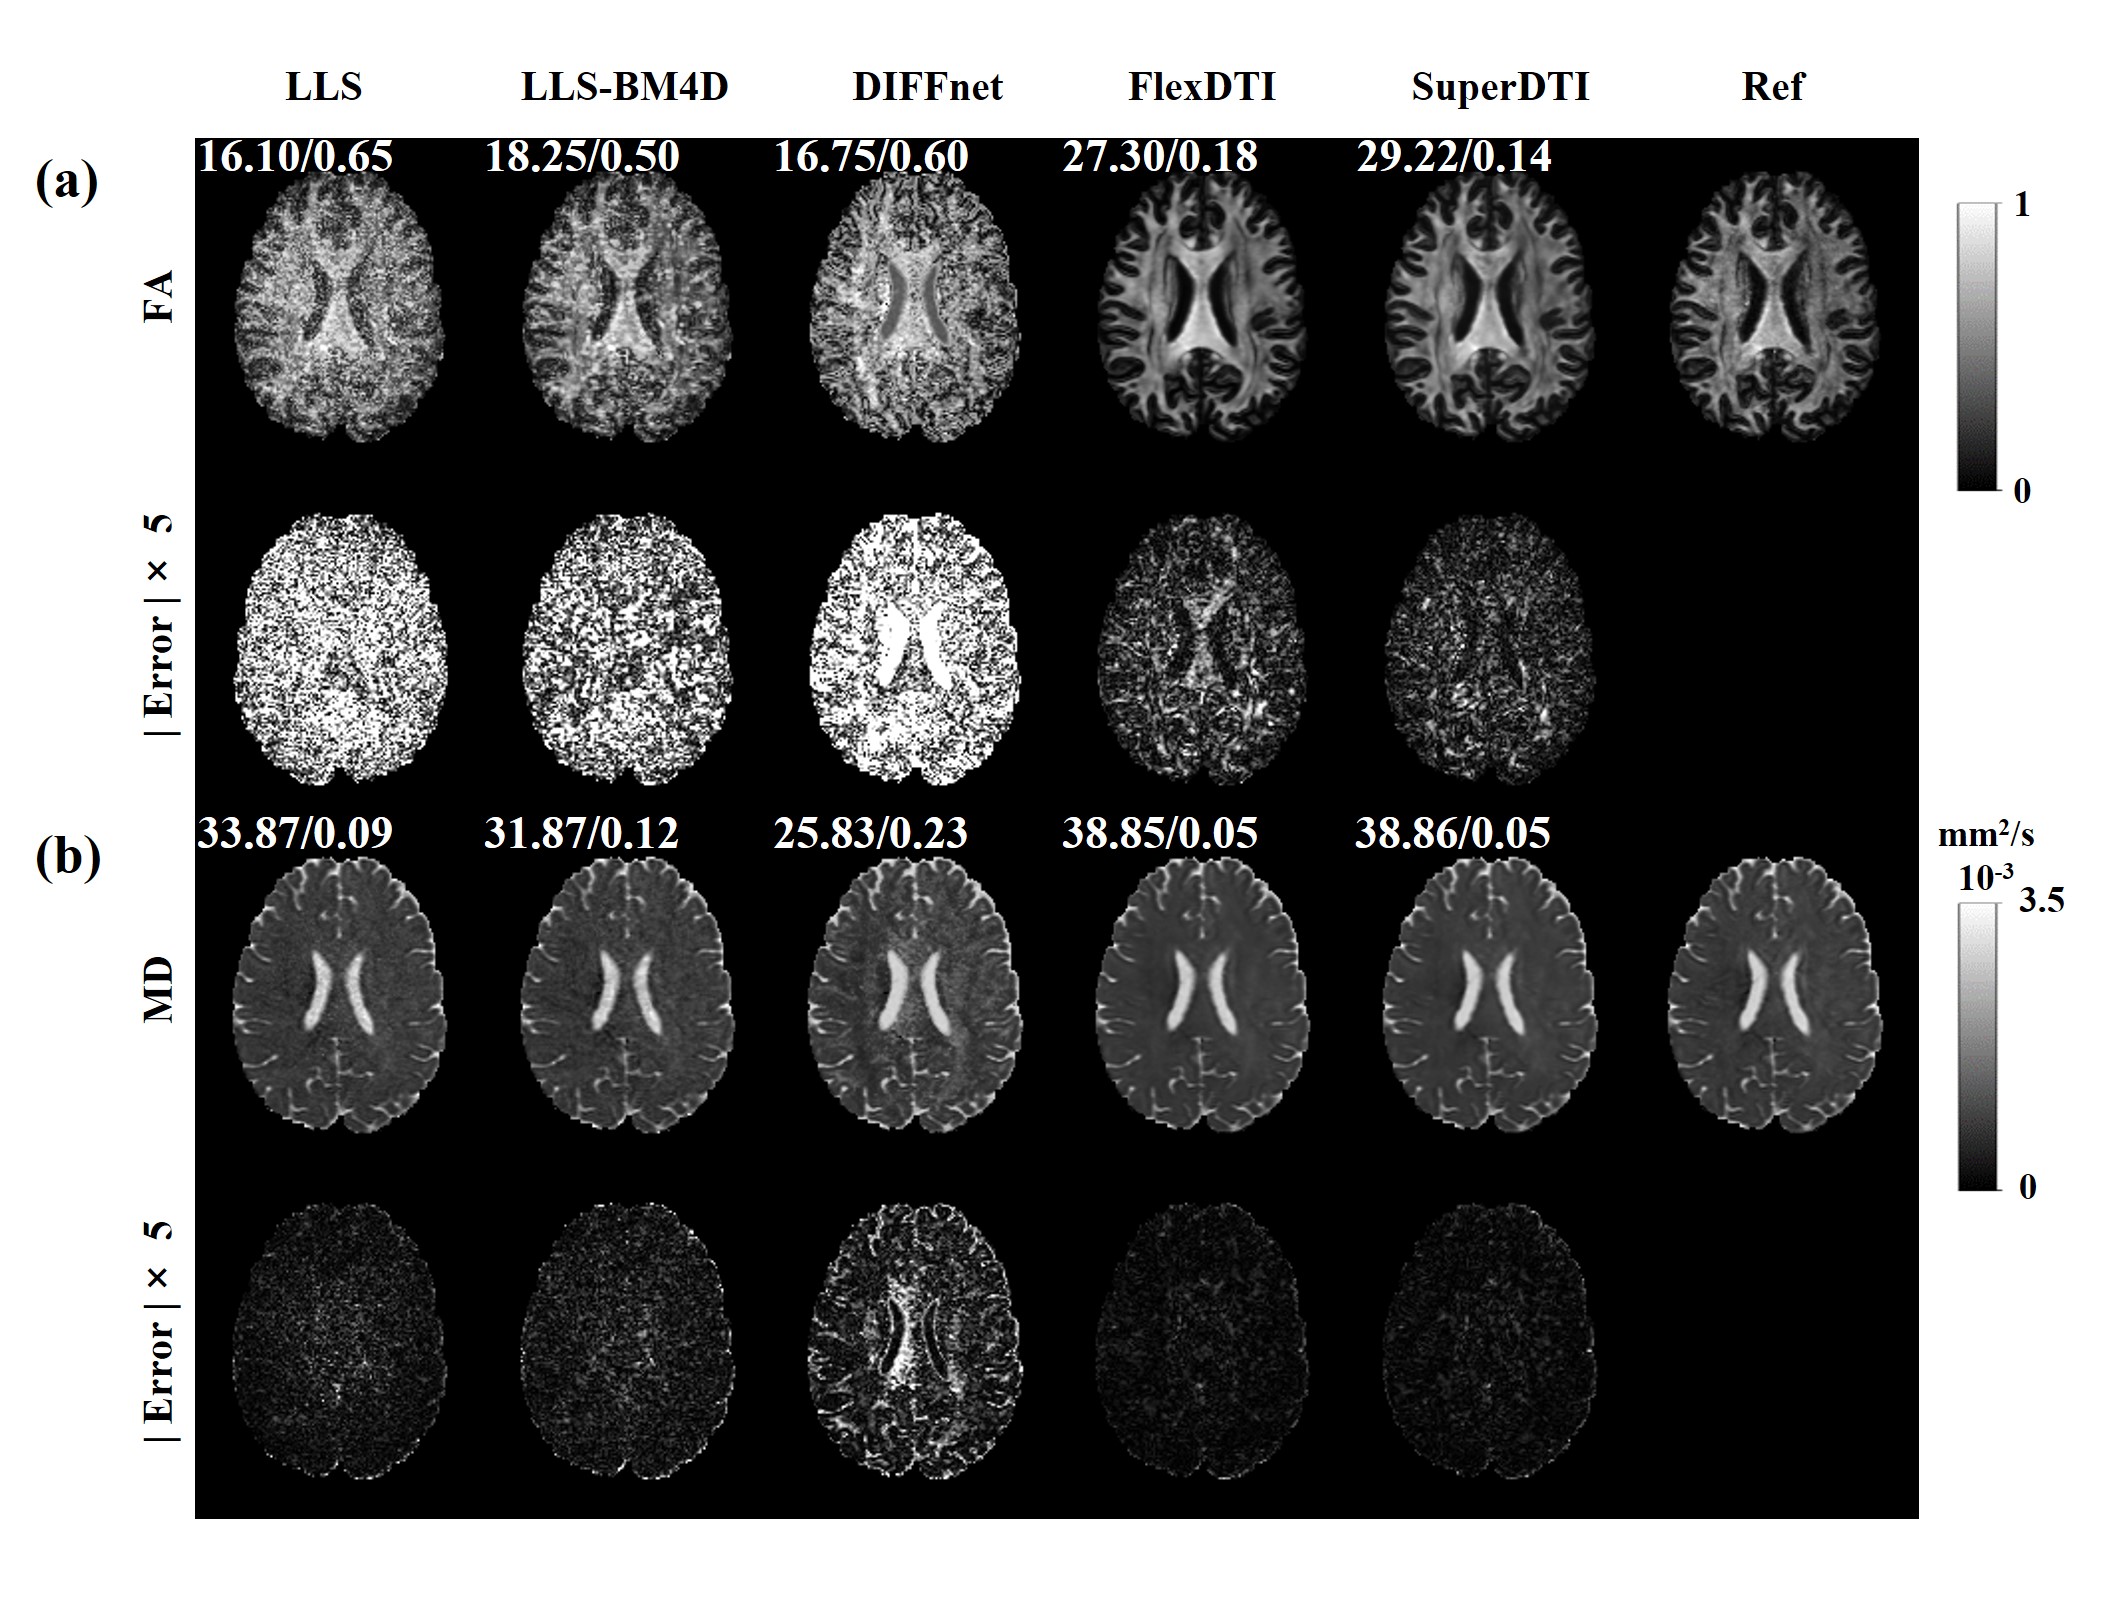

3.1 DTI reconstruction with flexible diffusion gradient directions

The results of four estimated tensor-derived parameters, i.e., FA, MD, AD and RD through different reconstruction methods were provided in Figure 2, where 6 DW images with flexible diffusion gradient directions were involved in the reconstruction. In terms of the reconstruction quality of the four quantitative parameters, FlexDTI has significant performance improvement compared with the other methods. The images from FlexDTI appear less noisy than others, with details more similar to the reference images. It is worth pointing out that 6 DW images are not sufficient to reconstruct high-quality DTI for DIFFnet method, while the proposed method can achieve high-quality DTI quantitative maps using only 6 DW images with flexible diffusion gradient directions.

Figure 2: Four parametric maps (FA, MD, AD and RD) reconstructed by LLS, LLS-BM4D, DIFFnet and FlexDTI using 6 DW images with flexible diffusion gradient directions. The references were reconstructed by LLS using 90 DW images. The PSNRs and NRMSEs are given at the upper left corner of each reconstruction image.

Table 1 presents the mean ± standard deviation of PSNR, SSIM and NRMSE for the data collected from 21 volunteers. These metrics correspond to the four estimated tensor-derived parameters obtained through four different methods. Compared to DIFFnet, FlexDTI reduces NRMSE by 0.54, increases PSNR by 8.15 dB and SSIM by 0.17 on FA, and reduces NRMSE by 0.17, increases PSNR by 10.36 dB and SSIM by 0.05 on MD.

Figure 6 shows the reconstructed results of two estimated tensor-derived variables, i.e., FA and MD from all methods. Compared to SuperDTI, FlexDTI showed a mild performance decline in FA reconstruction (-1.92 dB in PSNR and +0.04 in NRMSE) and was nearly consistent in MD reconstruction. This means that FlexDTI achieves good flexibility without sacrificing too much reconstruction quality.